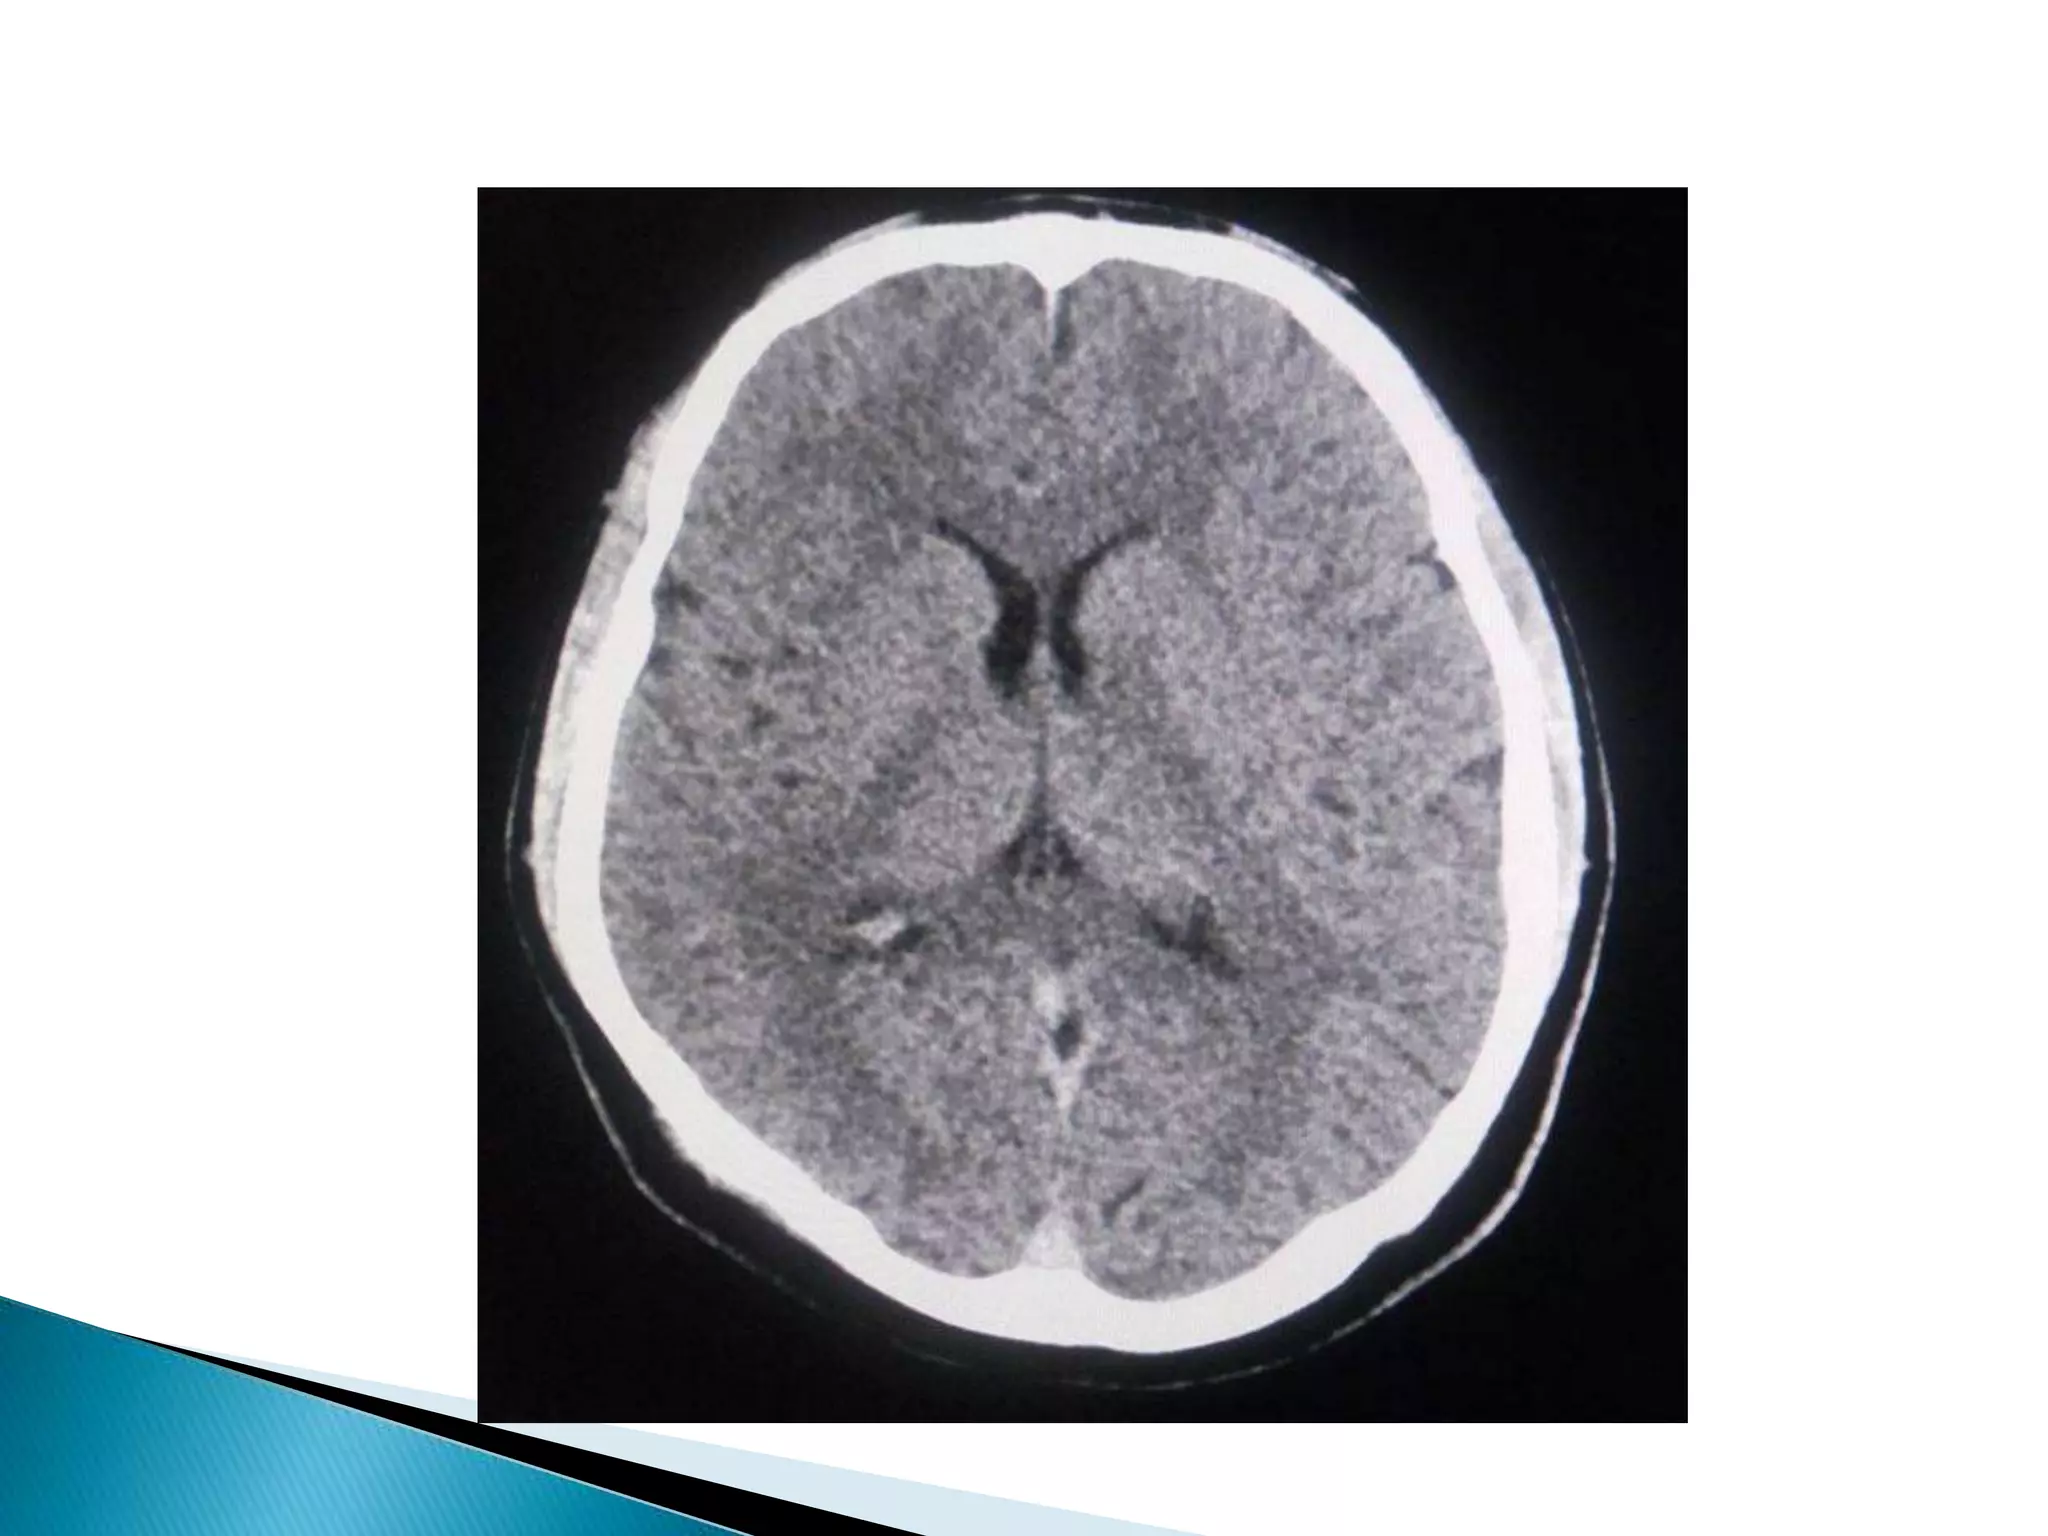

 His CT Brain, MRI Brain ( DWI ) didn`t show

any abnormality